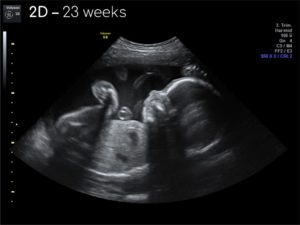

23 Недели 2 дня беременности

Когда беременность достигла срока 23 недели, ваш малыш весит 607 грамм. Его рост колеблется от 28 до 30 см. Размер плода можно сравнить с кукурузой. Вы можете сравнить снимки первого УЗИ и второго. Впечатляет, как за это время ребенок изменяется, сколько стадий развития он проходит.

Основной задачей ультразвукового исследования в текущие дни является определить чистоту околоплодных вод, состояние матки и положение плаценты. УЗИ покажет, как развивается малыш, соответствуют ли антропометрические данные сроку вынашивания.

- УЗИ: в этот период беременности врач может достаточно точно определить пол ребенка, хотя в редких случаях возможны ошибки.

Гинекологи советуют делать второй скрининг как раз в период с 21 по 23 недели беременности.

Во время второго ультразвукового исследования мамочка может много чего узнать о своем малыше и даже сделать его снимок.

Назначают его, чтобы полностью осмотреть опорно-двигательный аппарат и внутренние органы плода. Нужно исключить все риски возможных врожденных болезней и пороков и если что, то назначить необходимое лечение.

Врач-сонолог полностью описывает каждый орган маленького человечка, количество околоплодных вод, дает оценку пуповине и описывает параметры матки беременной.

Каждый ребенок после 23 недели беременности начинает индивидуальное развитие. Уже нет привычных норм веса и других параметров. Поэтому нужно внимательно исследовать мозговую активность, нужно посмотреть, чтобы не было никаких отклонений в развитии.

Обязательно врач прослушивает сердечко. Сердцебиение в идеале должно составлять 150-160 ударов в минуту.

Одно из главных – это осмотр плаценты, потому что это главный орган который связывает мать и ребенка. Врач измерят ее длину, расположение и, конечно же, степень зрелости. Он осматривает органы малого таза роженицы, и делает первые выводы о готовности женщины к родам.

Отдельно уделяют внимание длине шейки матки, потому что во время беременности она может, укорачивается. Так же смотрят на внутренний зев матки. Главное, чтоб на этом периоде он был полностью закрыт. Если есть небольшое открытие, то специалисты рекомендуют поставить специальное пластиковое кольцо для разгрузки и поддержания матки – пессарий.

Начиная с 23 недели, малыш уже должен лежать вниз головой, ну это может поменяться в течение беременности еще много раз. Если возникнут, на протяжении дальнейшего протекания беременности, определённые сомнения касательно ребёночка, процедуру узи лучше повторить.

Определяется пол ребенка еще на первом узи в 12 недель, но удостовериться в правильности сказанного можно на 23 недели. Пол малыша уже полностью виден.